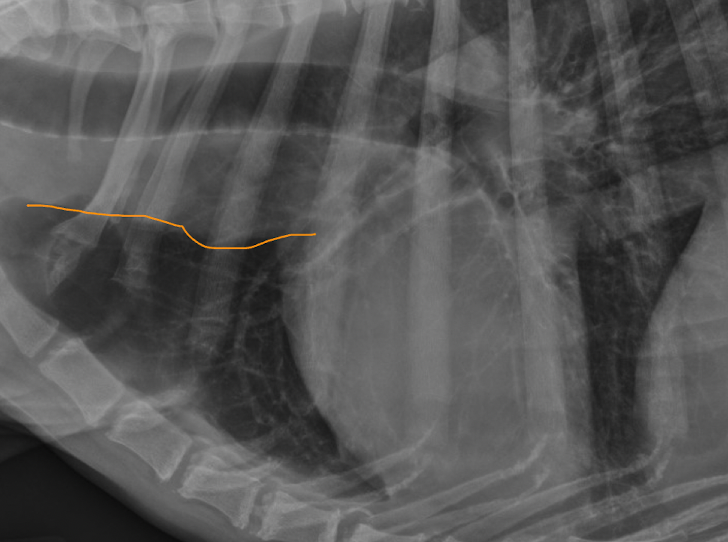

Q

mediastinal lymph node enlargement

ventral to trachea

+/- dorsal tracheal displacement

wide/convex cranial mediastinum (not straight line)